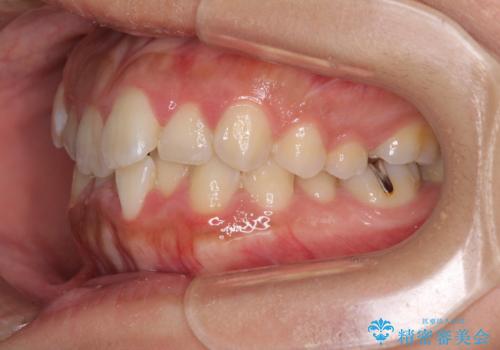

前歯のデコボコをインビザラインでスッキリと

- 上下前歯のデコボコを気にして来院された患者様です。

デコボコを解消する過程で、歯列の拡大により口元が突出する可能性があったため、4本の親知らずを抜歯しておき、歯列全体が後方に移動するように設計し、インビザラインにて矯正治療を行うこととしました。

日々の装着時間をしっかりと守って治療の臨んでくださったため、治療前のシミュレーションに近い形で矯正治療を進めて行くことができました。